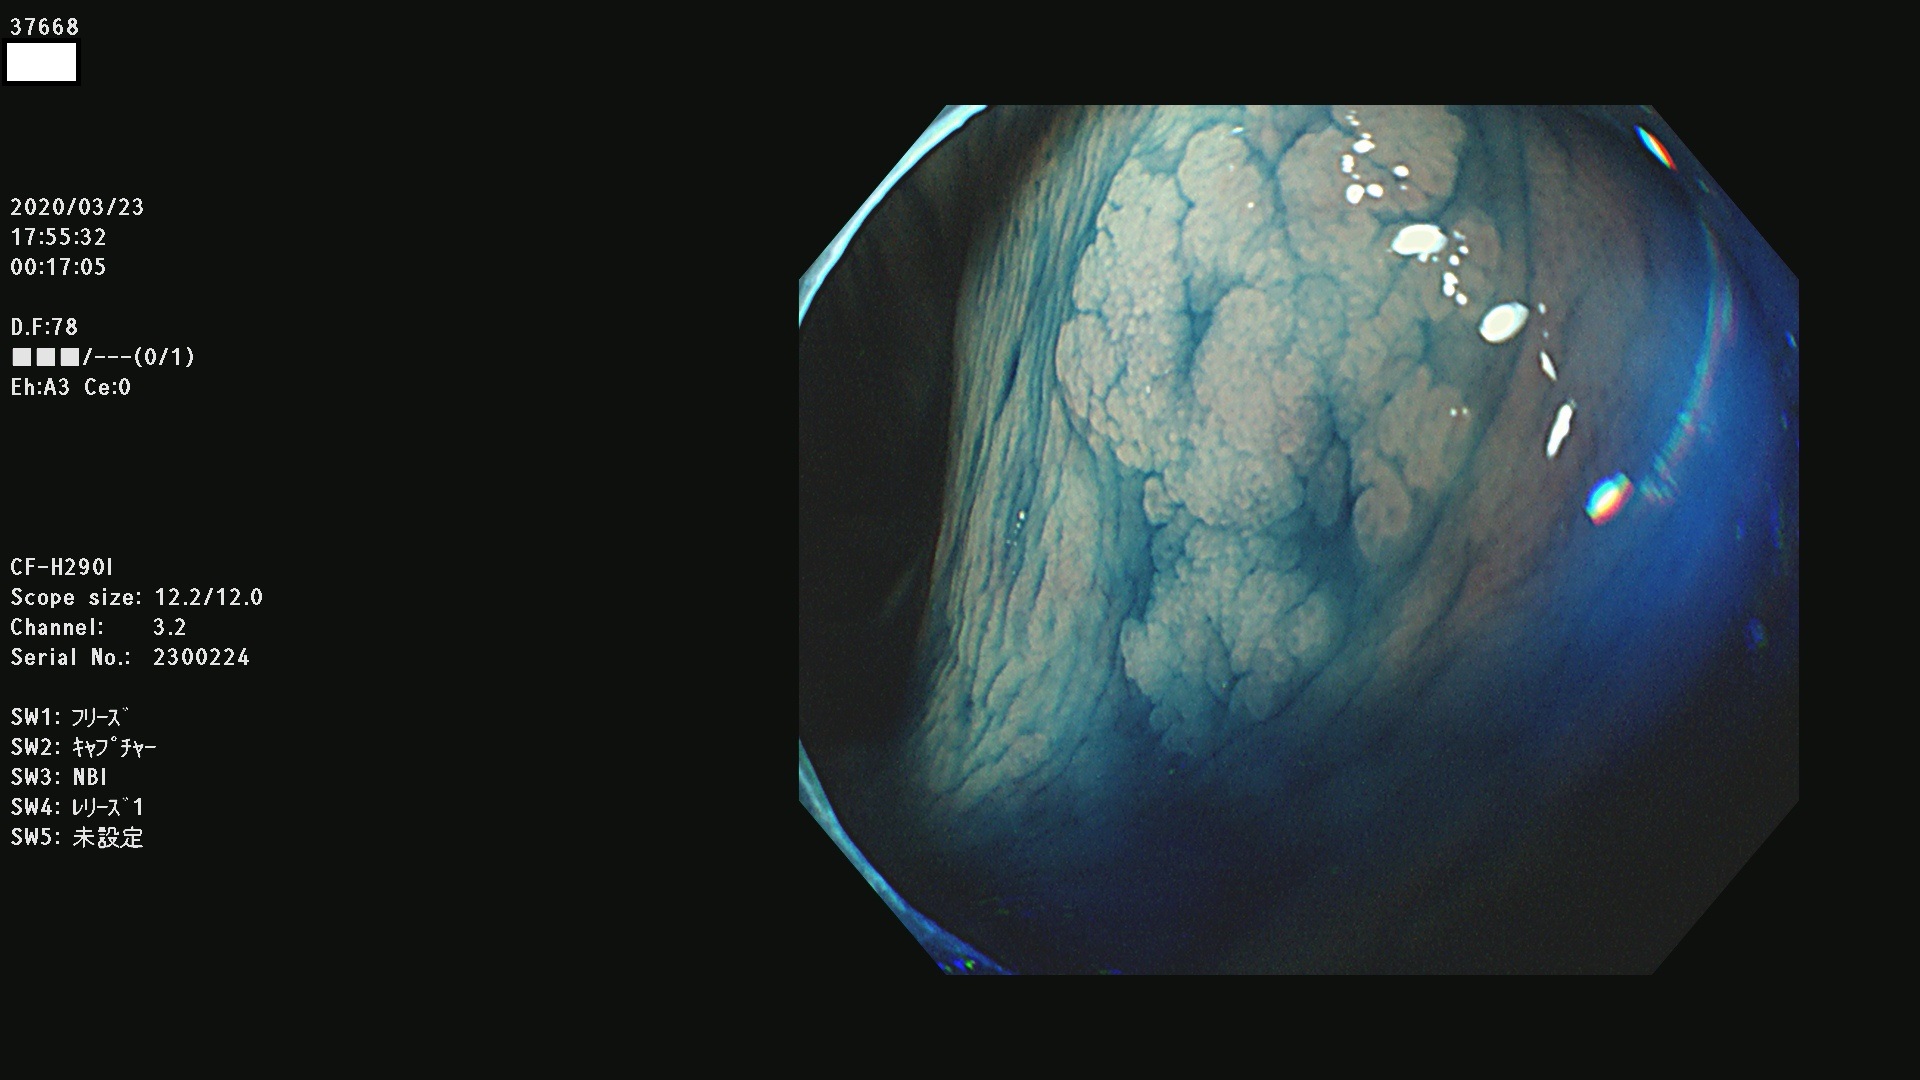

発見困難で危険性の高い平坦型病変(上記100名より抽出)